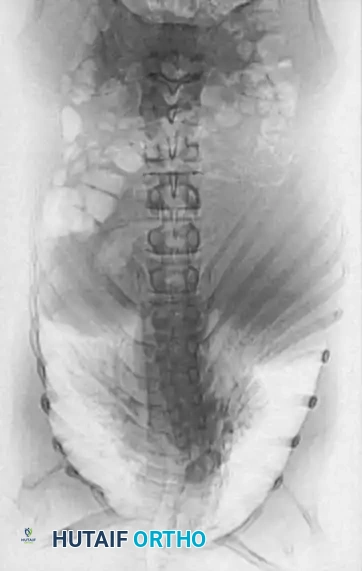

Phase 3: Posterior Instrumented Fusion

1. Instrumentation: Pedicle screws and/or hooks are placed. The posterior construct must be longer than the anterior fusion, typically extending at least one normal vertebra above and below the anterior graft.

2. Correction Mechanics: Only compression forces are applied across the posterior construct to close the posterior elements and hinge on the anterior strut graft. Distraction is strictly contraindicated.

3. Fusion: Copious autograft is applied following meticulous decortication.

Surgical Diagram: Posterior Instrumentation

Surgical Diagram: Rod Contouring

Surgical Diagram: Final Construct